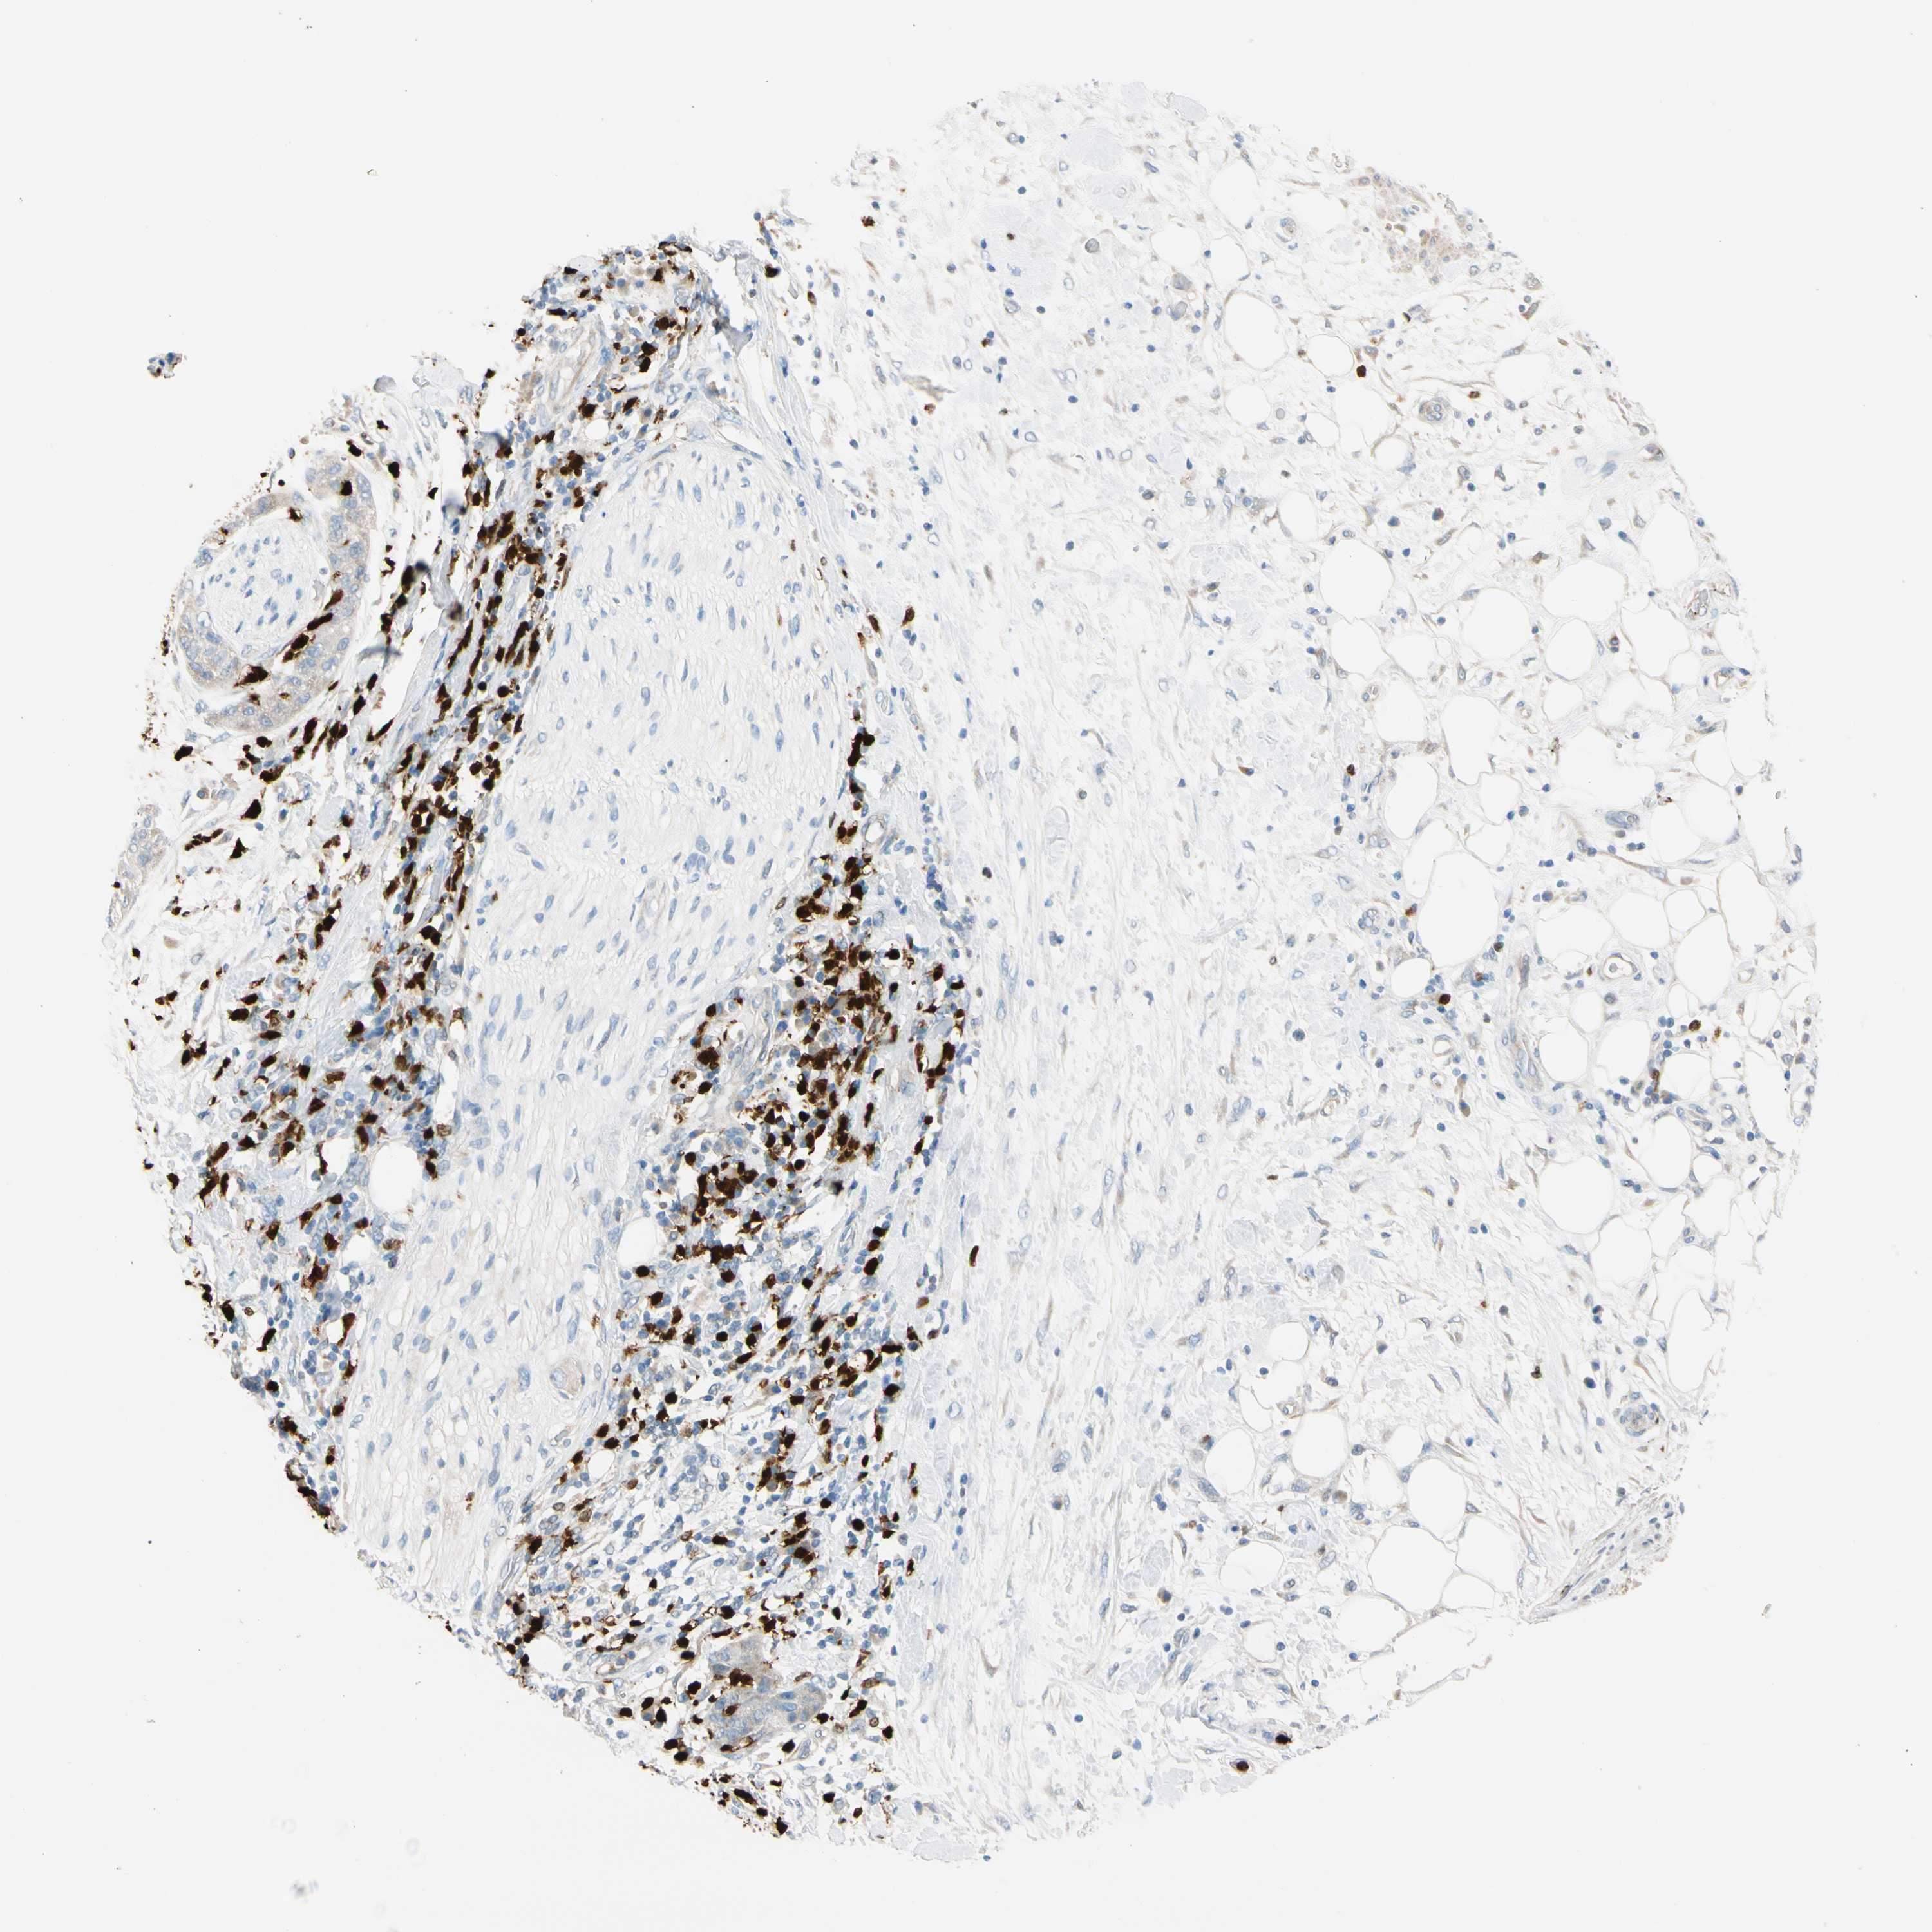

PANCREATIC CANCER - Protein expressioni

A mouse-over function shows sample information and annotation data. Click on an image to view it in a full screen mode. Samples can be filtered based on level of antibody staining by selecting one or several of the following categories: high, medium, low and not detected. The assay and annotation is described here.

Note that samples used for immunohistochemistry by the Human Protein Atlas do not correspond to samples in the TCGA dataset.

Antibody stainingi

Antibody staining in the annotated cell types in the current human tissue is reported as not detected, low, medium, or high, based on conventional immunohistochemistry profiling in selected tissues. This score is based on the combination of the staining intensity and fraction of stained cells.

Each image is clickable and will lead to virtual microscopy that enables deeper exploration of all samples and also displays staining intensity scores, fraction scores and subcellular localization as well as patient and tissue information for each sample.

Antibody HPA008052

Antibody CAB010277

Staining

High

Medium

Low

Not detected

Intensity

Strong

Moderate

Weak

Negative

Quantity

>75%

75%-25%

<25%

None

Location

Nuclear

Cytoplasmic/membranous

Cytoplasmic/membranous,nuclear

Adenocarcinoma, NOS

Adenocarcinoma, metastatic, NOS